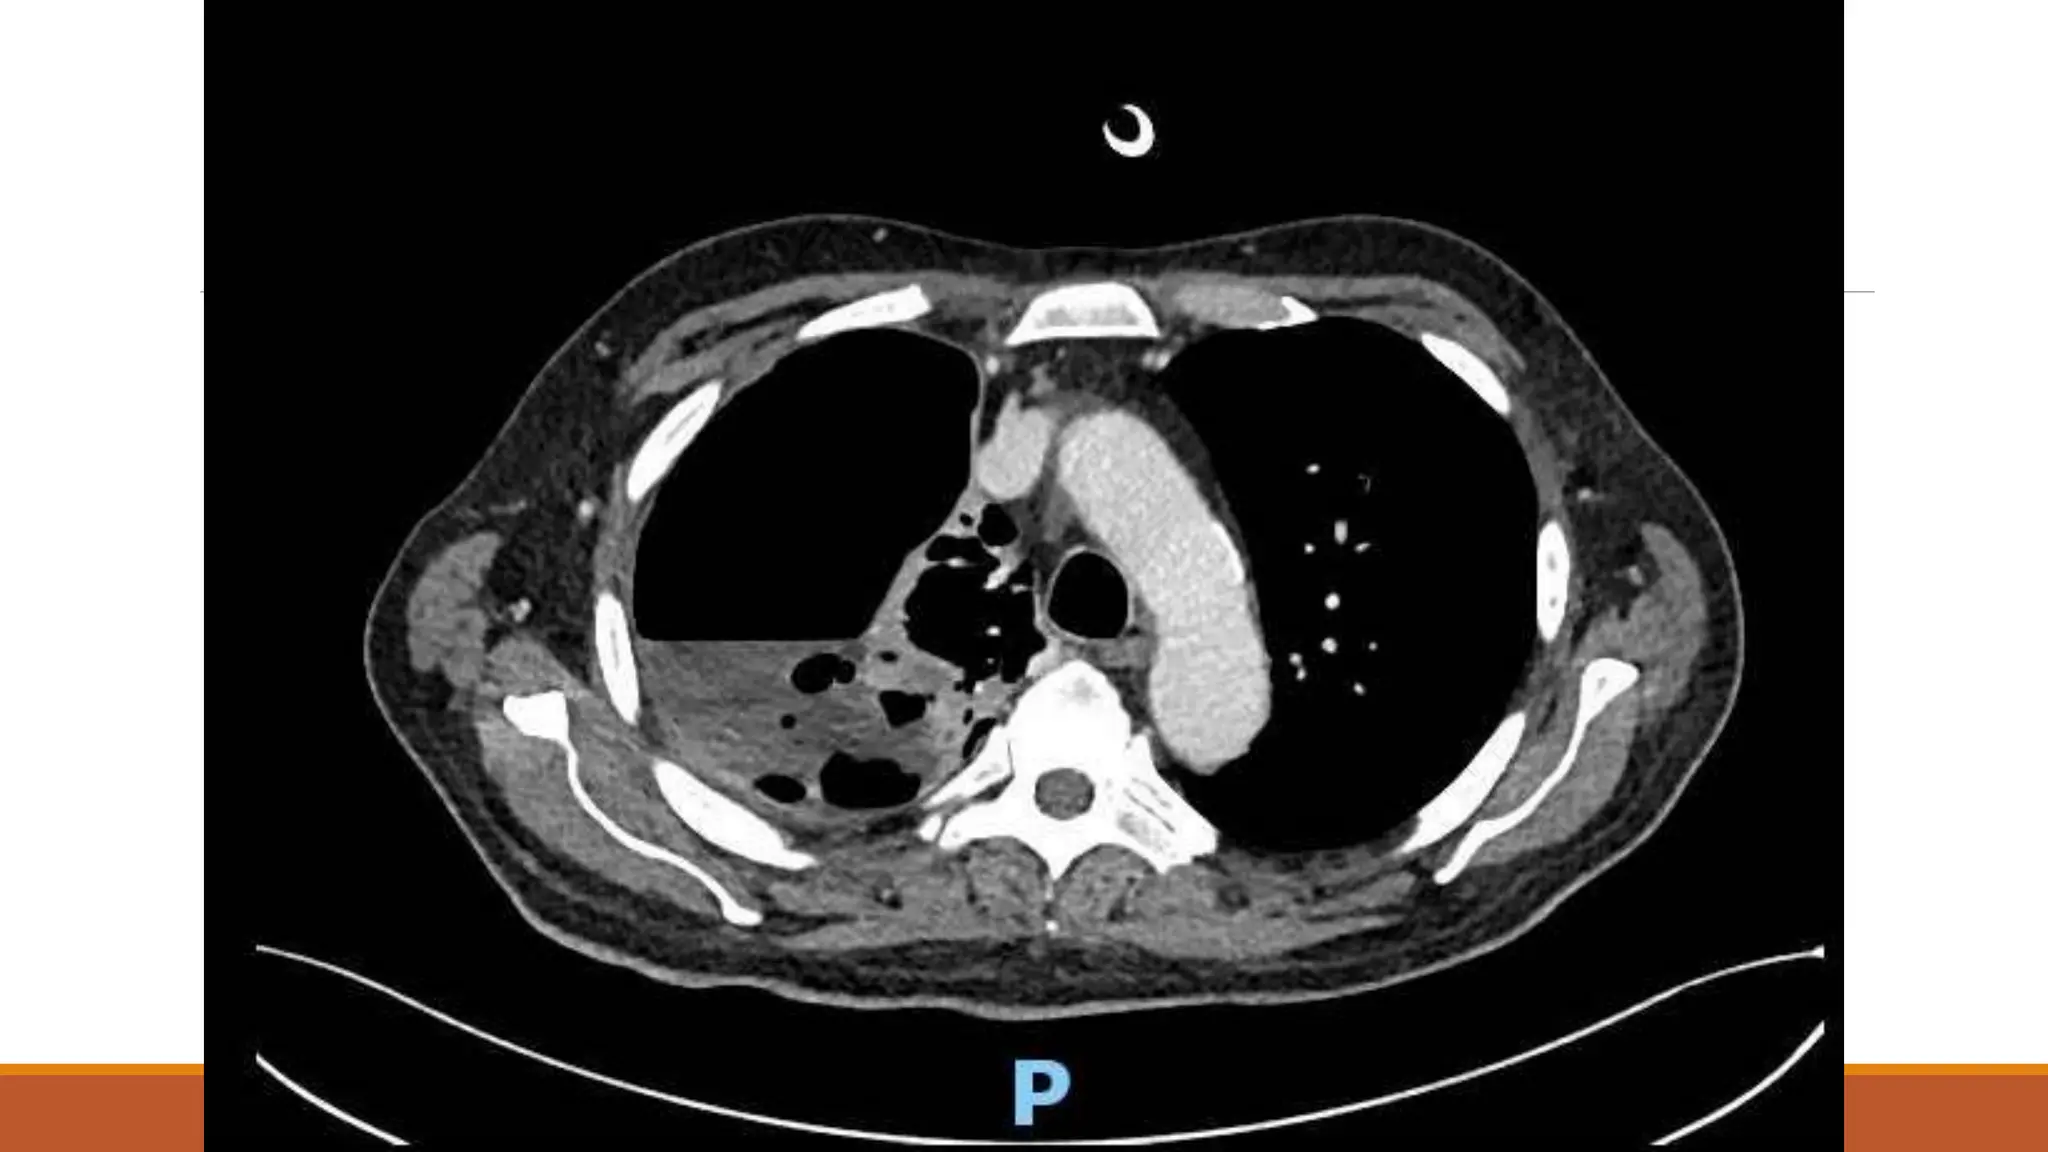

63 male

Normally F&W, no regular medications

Became unwell 7th Dec 2020 – cough, yellow sputum

Saw GP 23rd Dec – oral doxy

No real improvement – Clarithromycin 6/1/21

Again no improvement

Progressive loss of appetite and weight over a couple of months – given fortisip, which stopped

weight loss, but poor appetite continued

Progressive right shoulder pain and inability to lie on left side due to dyspnoea

On examination

OE: Acutely distressed, in significant pain and sats dropped to 80% when sat forwards, but 98%

when reclined at 60 degrees

Chest – no air entry right side

Results Fluid LDH >50000 pHunable due to viscosity Protein 63 Glucose <0.6 Fluid grew Streptococcus anginosus